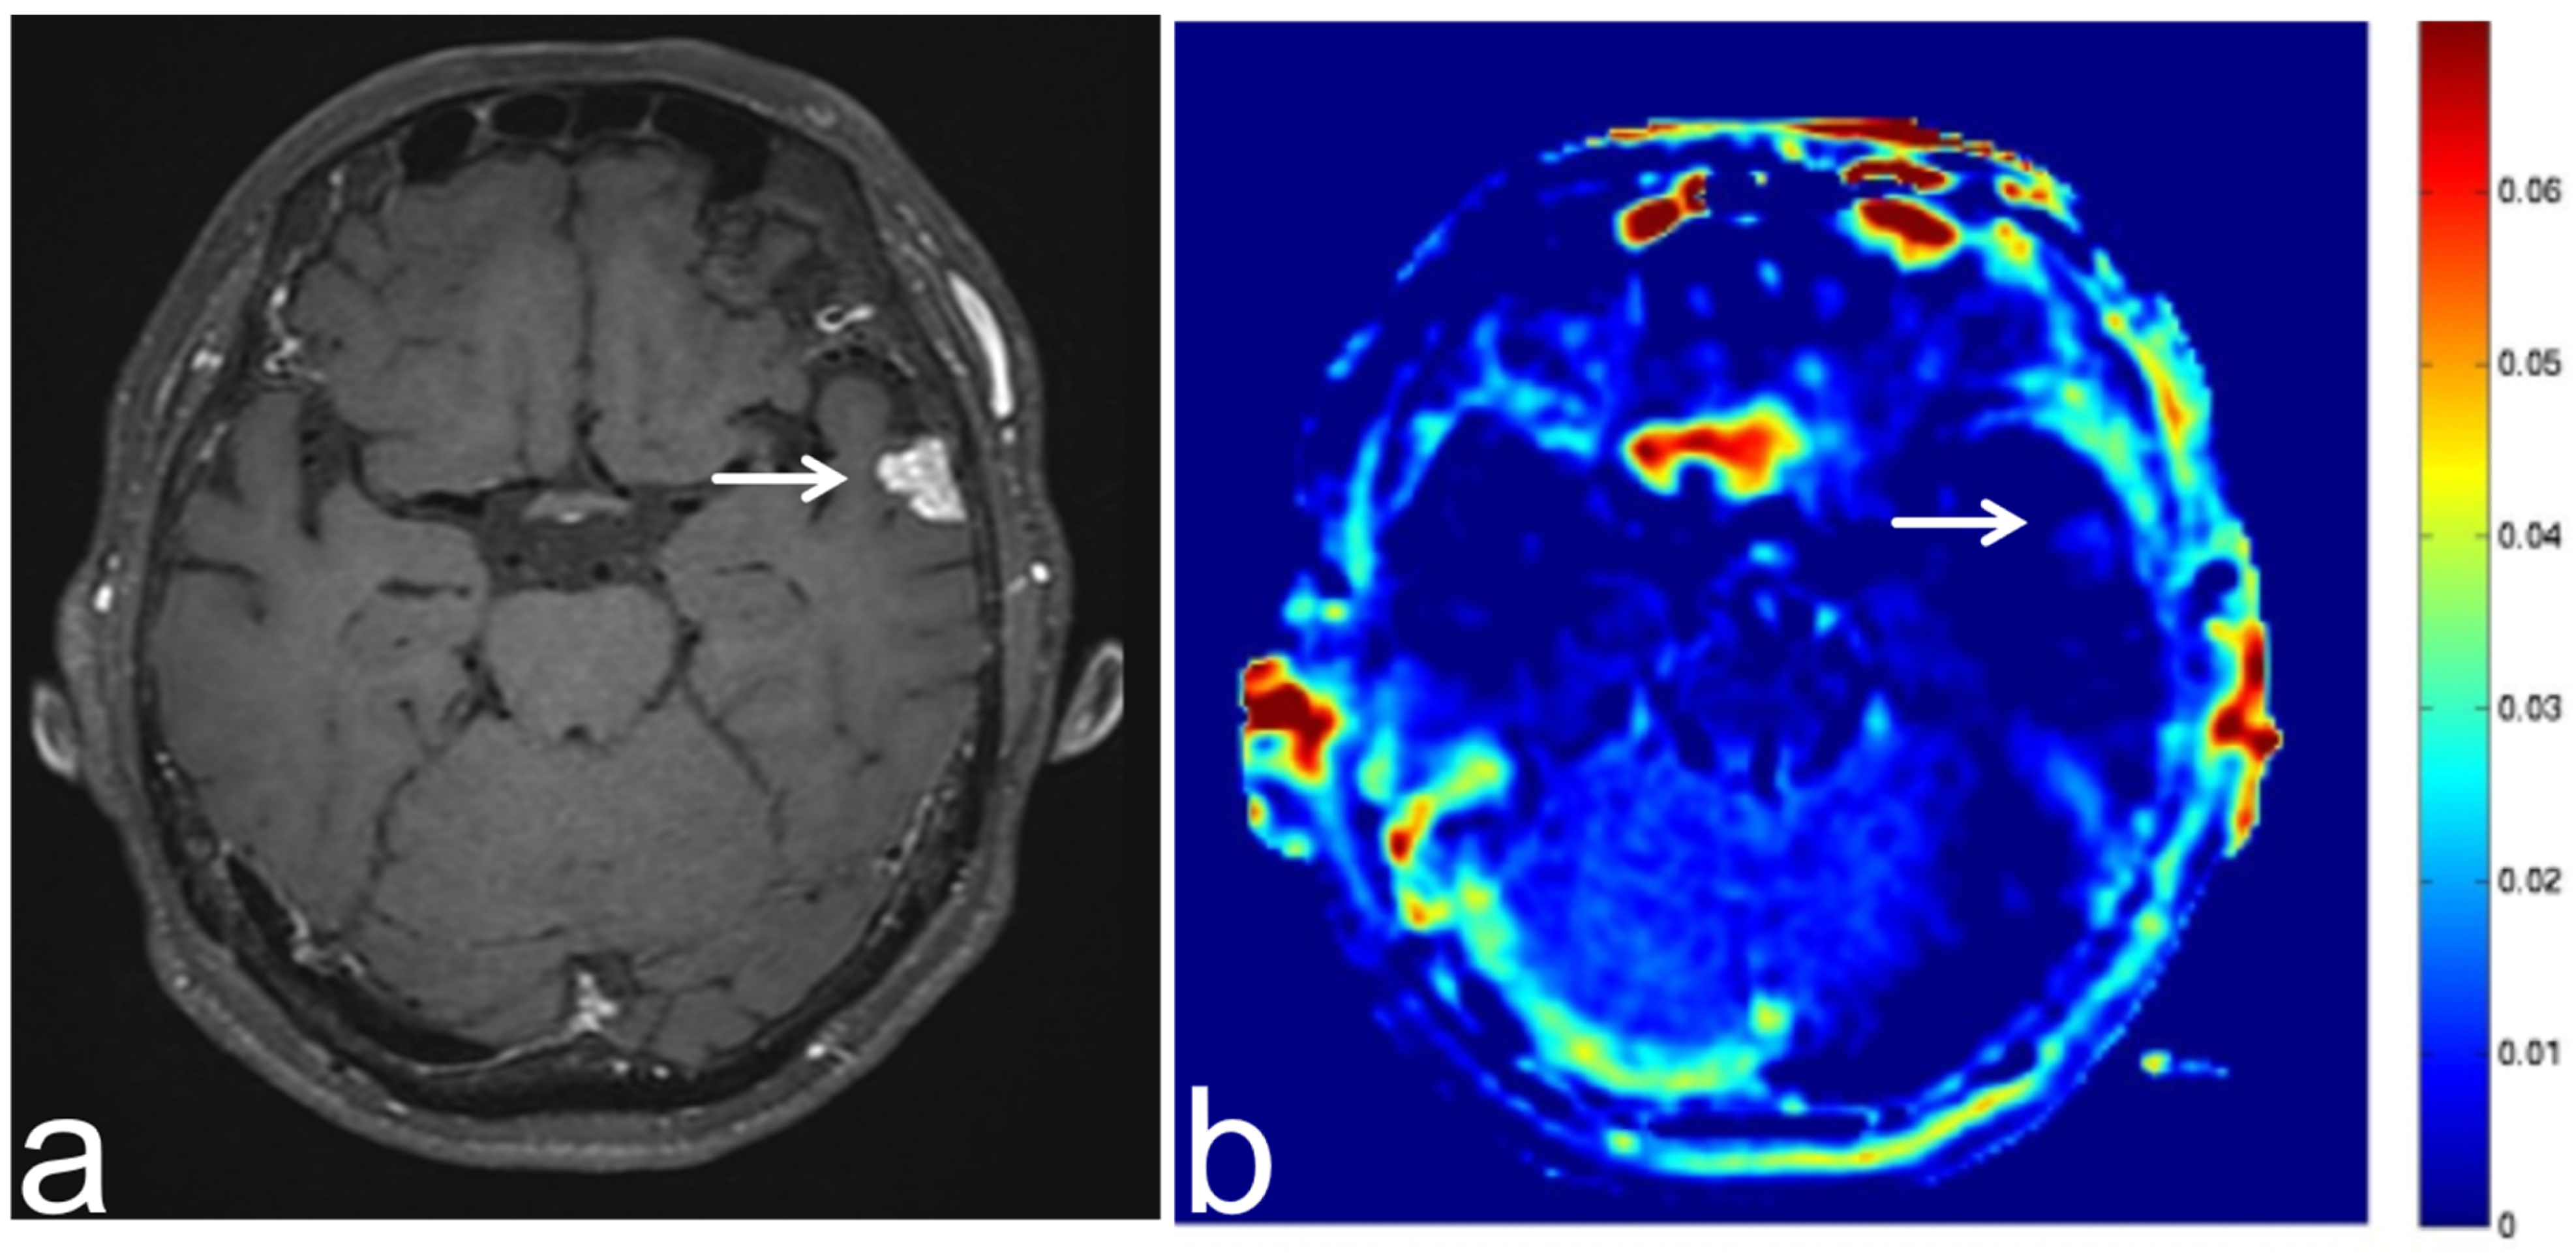

7.2. Solitary Fibrous Tumor